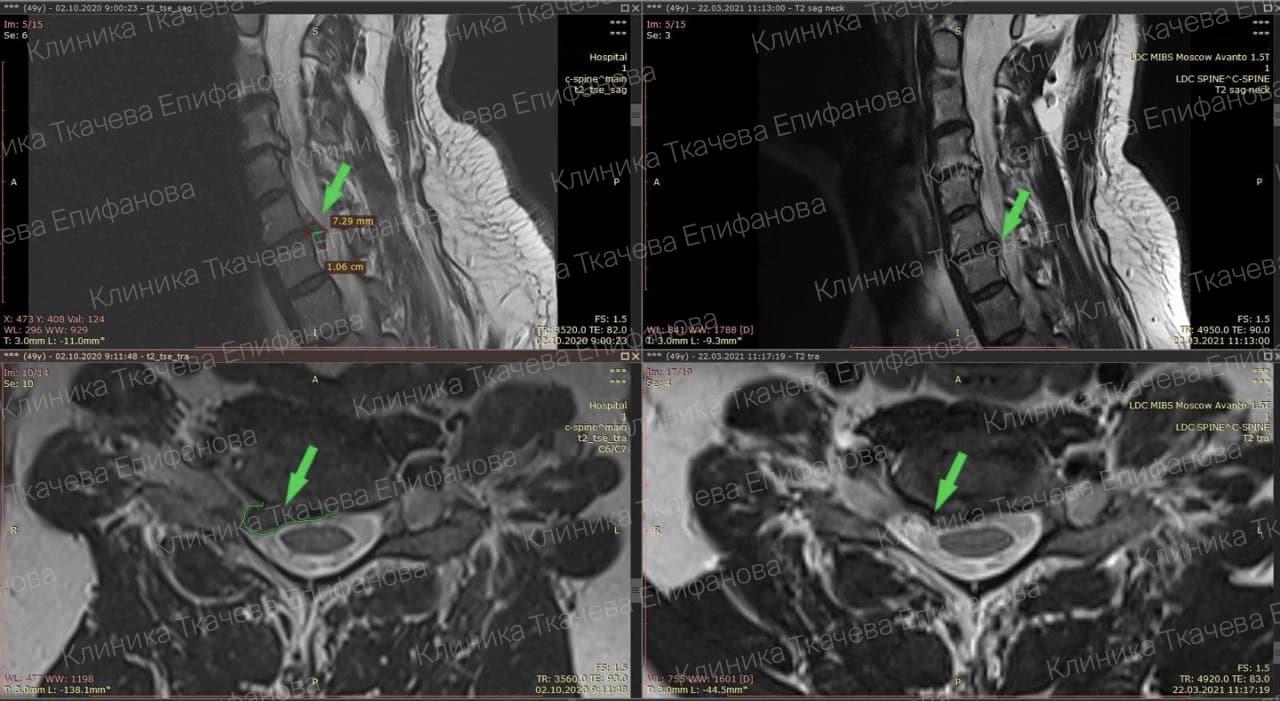

* Резорбция — процесс уменьшения грыжи диска за счет естественных физиологических способностей организма. Это основа эффективного лечения грыжи и альтернатива операции.

Метод модулируемой резорбции позволяет ускорить этот процесс, взять боль под контроль и улучшить качество жизни.